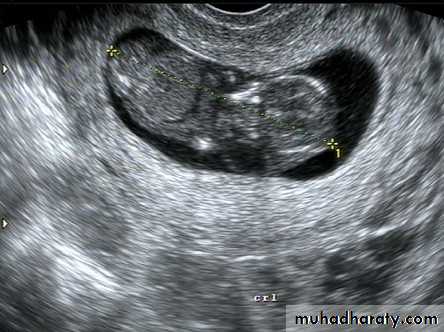

This is U/S of a patient presented with oligomenorrhea and infertility.

1. What is this gynecoiogical problem?2. List 3 other possible clinical presentation of this condition?

3. List 2 main hormonal changes?

P.C.O Syndrom

Oligomenorrea or amenorrhea, obesity and infertility.Inverse LH/FSH rato and increase test.level.